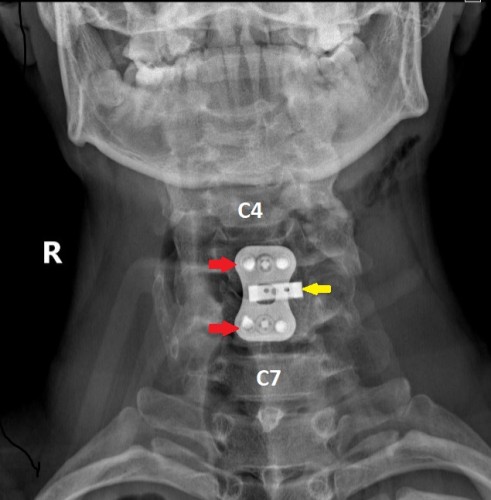

Заходя в оперблок, нейрохирурги уже знали, что будут делать. Под увеличением, с использованием операционного микроскопа, через небольшой разрез кожи по передне-боковой поверхности шеи была удалена травматическая грыжа диска. Затем, под рентген-контролем был успешно вправлен вывих, а позвонки зафиксированы при помощи титанового кейджа и пластины.

После операции – прямая проекция